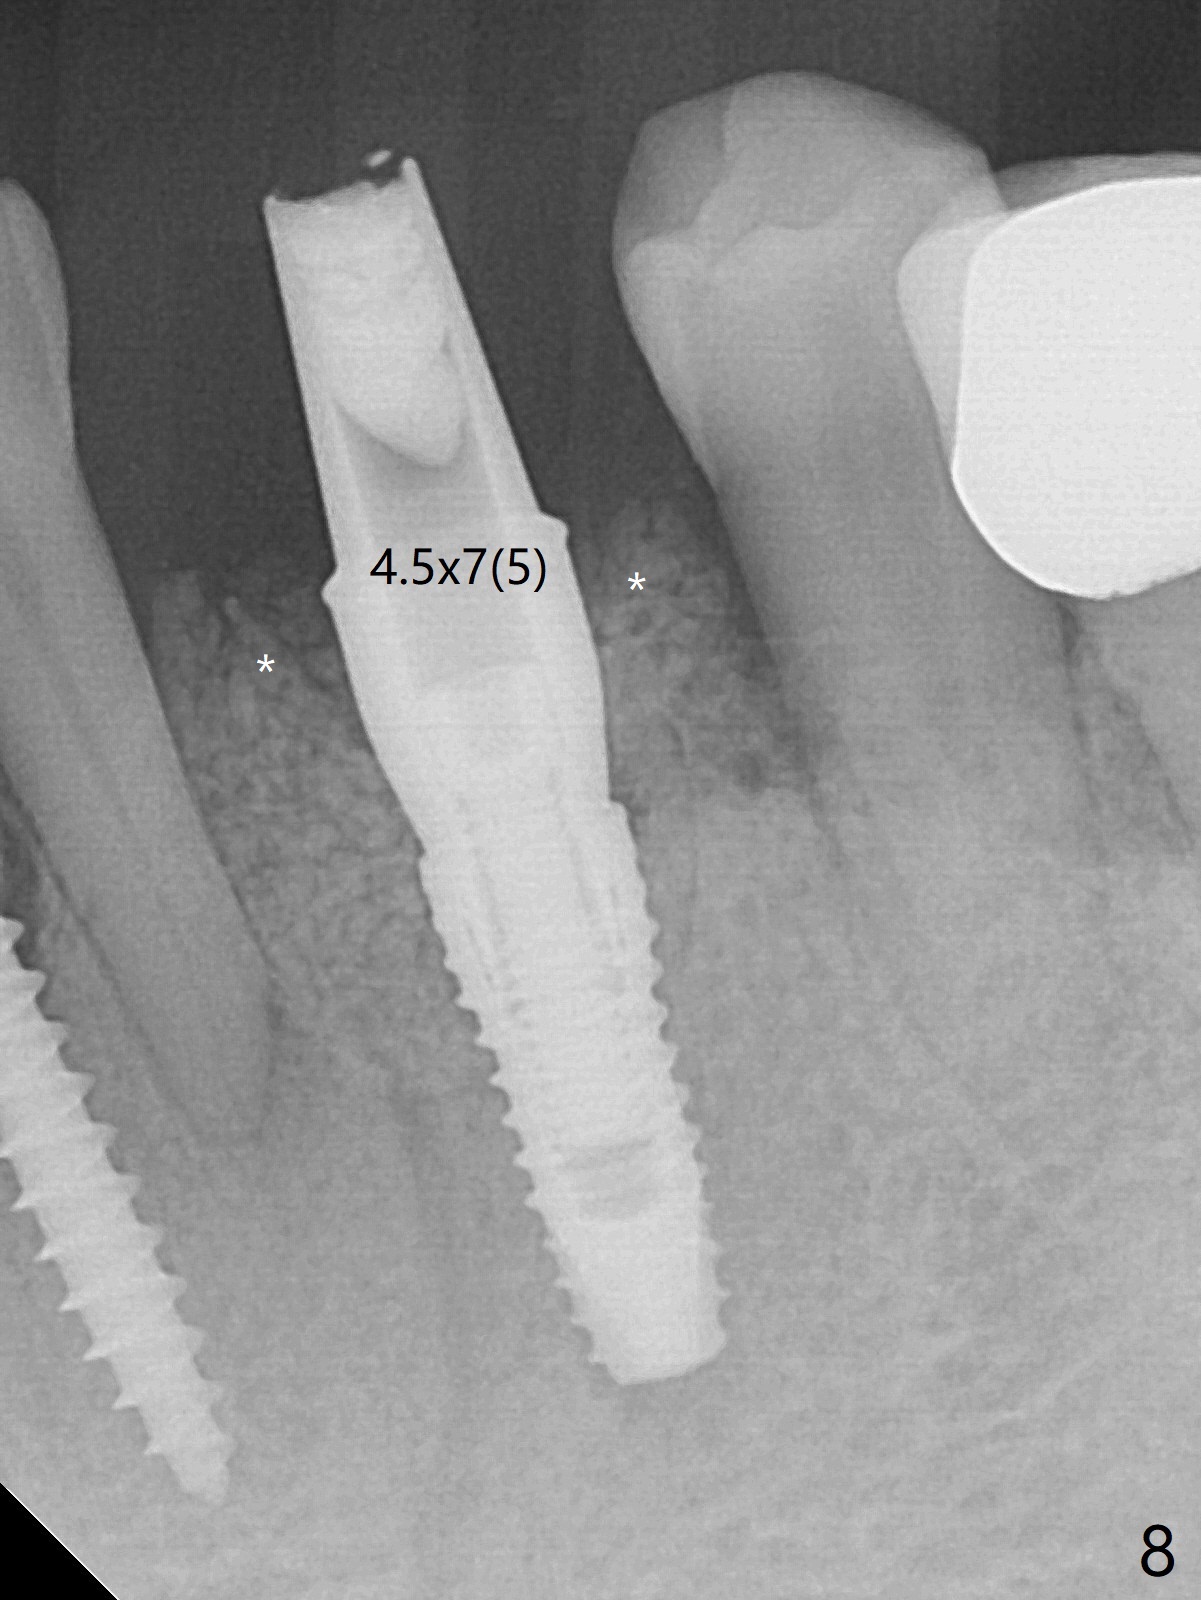

There is a fistula buccal to the apex of the tooth #23 preoperatively (Fig.1), which is related to loss of the buccal plate of the socket of #23. Therefore an implant is placed mainly in the socket of #22 (Fig.3). The lingual (Fig.2 L) gingiva appears to have more extensive inflammation. After extraction, the lingual (Fig.3 L) gingival margin is significantly lower than the buccal one. The lingual crest is ~ 4 mm lower than the buccal one. A 3.8x10 mm dummy implant is placed tentatively with an apical space (Fig.4). When a same dimension definitive implant is placed with 40 Ncm, it is 2 mm below the lingual gingival margin, whereas 6-7 mm below the buccal one (Fig.5). Vanilla graft is placed before placement of a 5.5x4(5) mm abutment (Fig.6,7). There is a 2-3 mm lingual (L) gap to be filled with the allograft secondarily to prevent periimplantitis (Fig.7). Later the abutment is changed to a longer and smaller one (Fig.8) with more of the allograft (*). After trimming of the abutment (Fig.9 (*: papilla between the fused teeth)), an immediate provisional is fabricated to close the socket (Fig.10, similar to Fig.1). The majority of the bone graft seems to be in place 8 months postop (Fig.12). The implant appears to have been placed buccal, consistent with the thin and slightly erythematous buccal gingiva (Fig.13). The ridge completely regenerates 2 years post cementation (Fig.14).